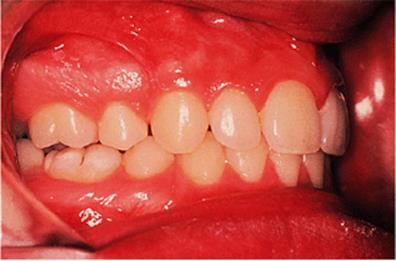

Before discussing functional appliances in detail, Fig. 18.1 gives an overview of this type of functional appliance in clinical use. This patient has a Class II division 1 malocclusion of the type for which functional appliances are very suitable, and for which they have been used for many years.

There are a number of important features to note which will be discussed further later in the chapter. First, the patient is still growing and the signs are that her pattern of facial growth is likely to be favourable. Although the skeletal pattern is Class II, the vertical relationships are close to average and the direction of mandibular growth is likely to be a mild forward rotation (see Chapter 4) which is favourable to the correction of a Class II malocclusion. Second, the soft tissue morphology is favourable despite the lips being incompetent, with the lower lip resting behind the upper incisors. The lower lip line is above the level of the upper incisal edges, and after the overjet has been reduced the lower lip will rest labially to the upper incisors, so helping to resist any tendency for relapse of the overjet. Third, the arches are well aligned — functional appliances have no mechanism for treating irregularities of alignment of the teeth.

Fig. 18.1. (a) This 12-year-old girl had a skeletal II facial pattern and average facial proportions. The lips were incompetent with the lower lip lying below the upper incisors at rest. (b), (c) She had a Class II division 1 malocclusion with an overjet of 10 mm, the overbite was increased and complete, and the molar relationship was Class II on both sides. (d), (e) The upper and lower arches were well aligned. (f) A functional appliance (an activator) was fitted. (g) The corrected occlusion with Class I incisor and molar relationships. (h) The patient's facial profile at the end of treatment.